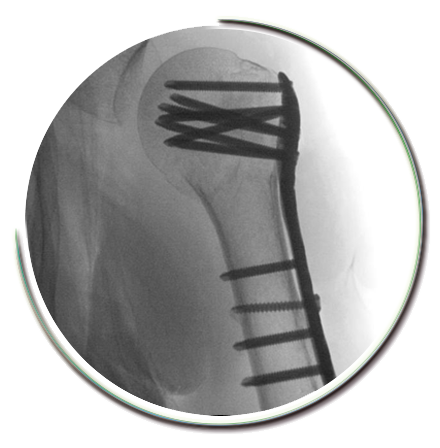

Omuz kırığı ameliyatı-Proksimal humerus kırığı ameliyatı ne zaman gerekir?

Parçalı kırıklarda, kaynama sorunları ve işlev kaybı oluşması nedeniyle cerrahi müdahale gerebilmektedir. Modern tespit metodları sayesinde, tespit gücü yüksek, erken rehabilitasyonun sağlanabildiği tedaviler yapılabilmektedir. Minimal invaziv kırık cerrahisi adı verilen bu metod ile kırık bölgesine zarar verilmeden doğal iyileşme süreci sürdürülebilmektedir.